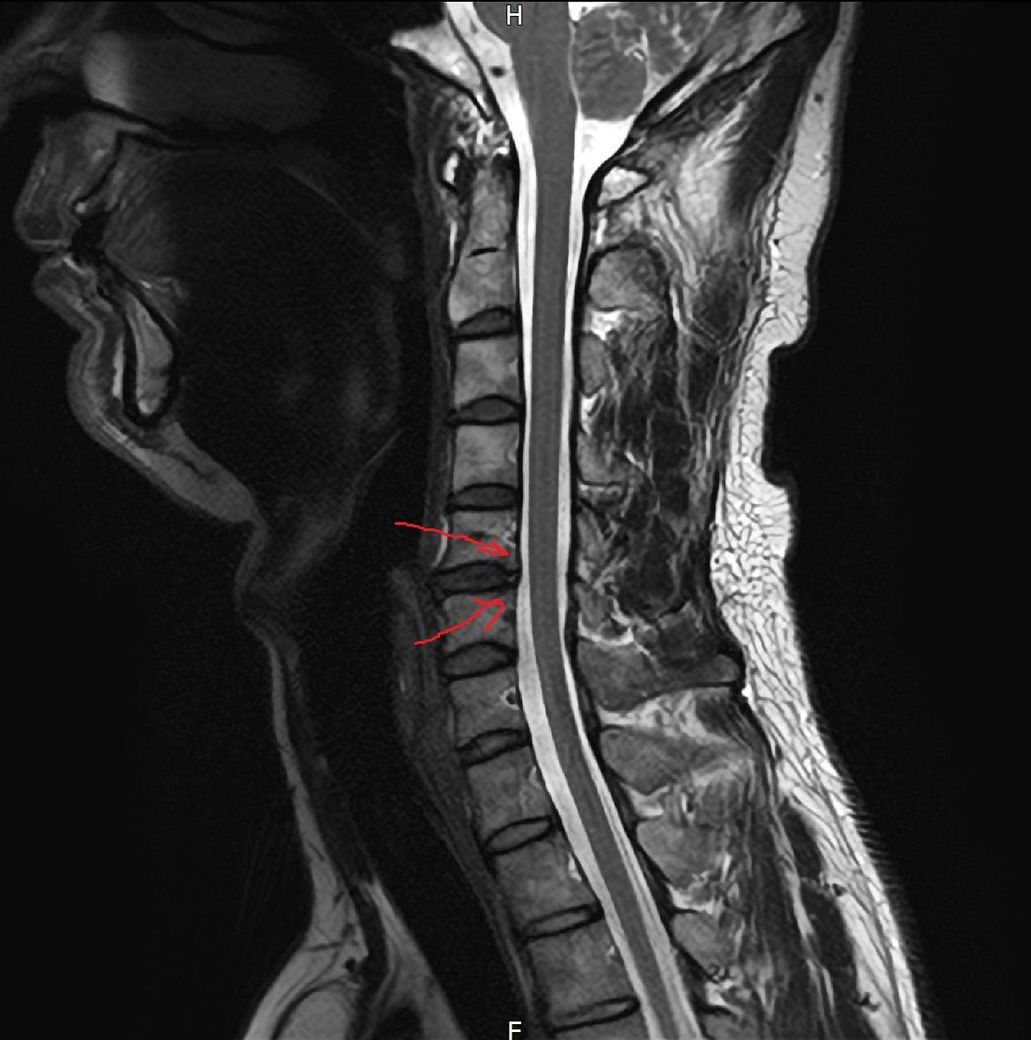

문제는 상체에서 끝나는게 아니라 3월중순쯤 길을 걷는데 발바닥 아치에서 모레알 밟는느낌이 나더니 이게 보름정도 지나고나서 양측성으로 나타나면서 모레알 밟는 감각이상의 느낌이 열감으로 바뀌더니 작열감으로 또 변질되고 앞꿈치 뒷꿈치 막 퍼지듯 하면서 왼쪽정강이쪽엔 벌레기어가는 그런느낌들고 허벅지에 따끔한 증상같은게 올라오고 엉치통증 허리통증 이런식으로 올라와서 허리문젠가 싶어서 mri를 찍어봣는데 목이나 허리나 퇴행변성같은게 포착이 되었지만 그게 신경을 누르는 상태는 또 아니였습니다. 허리와 목 mri 사진을 혹시 몰라서 첨부합니다.

목은 25년2월에 찍었고 허리는 25년5월,7월 2번을 연달아 찍었습니다. 왜냐면 하체증상으로 더 심하게 느낀 상태였기 떄문에